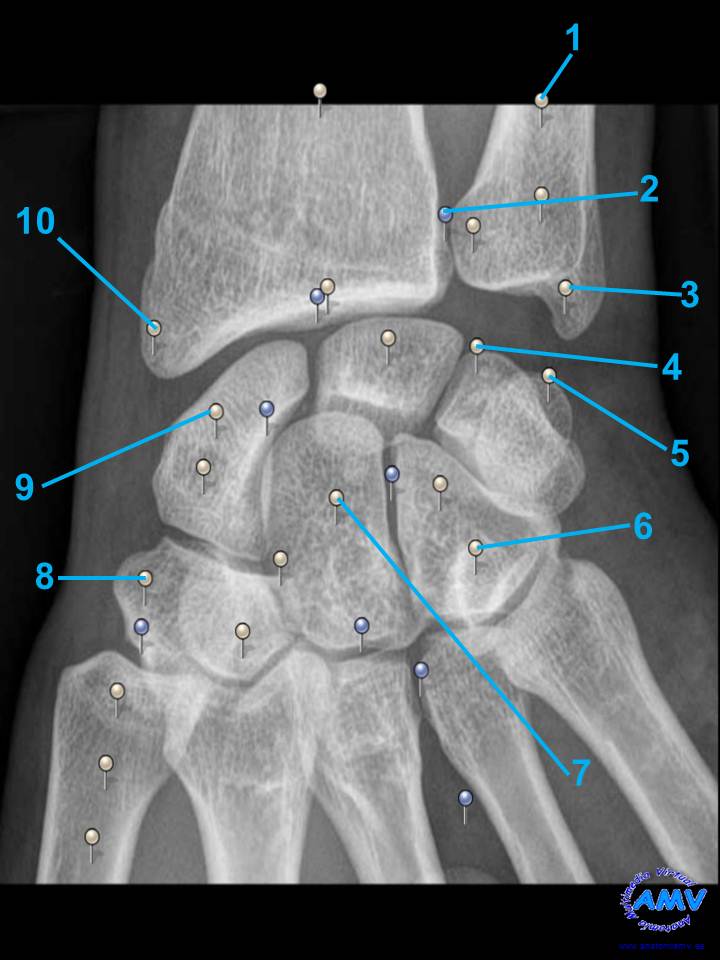

rx_ms_11.jpgIndique que estructura se señala con el número correspondiente:

El nº 1 señala .

El nº 2 señala .

El nº 3 señala .

El nº 4 señala .

El nº 5 señala .

El nº 6 señala .

El nº 7 señala .

El nº 8 señala .

El nº 9 señala .

El nº 10 señala .